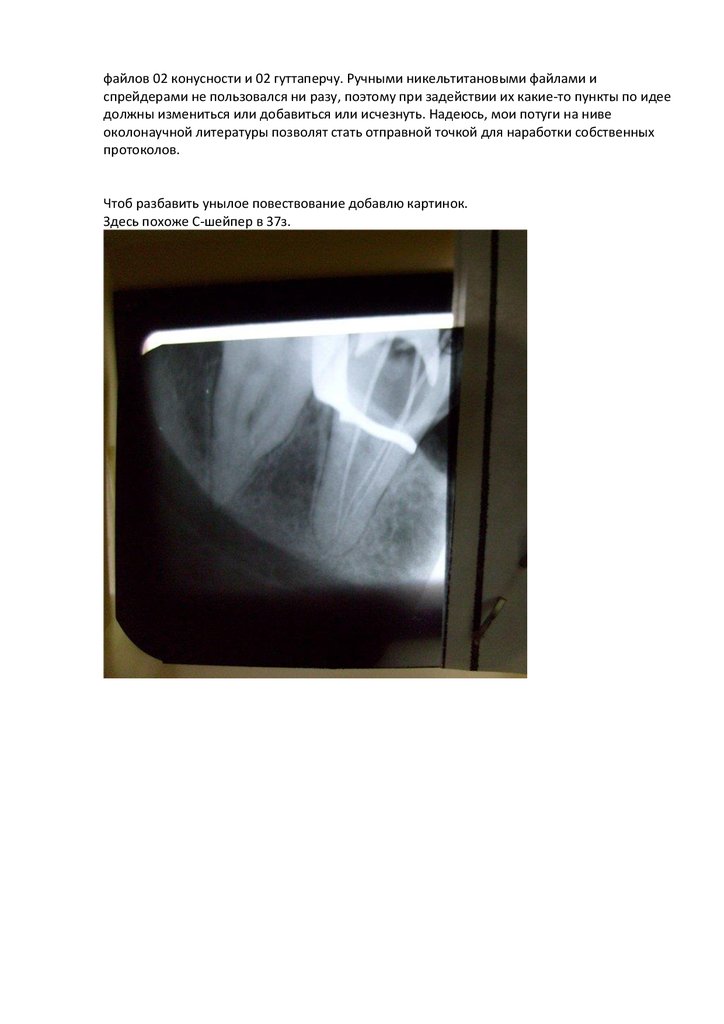

Чтоб разбавить унылое повествование добавлю картинок.

Здесь похоже С-шейпер в 37з.